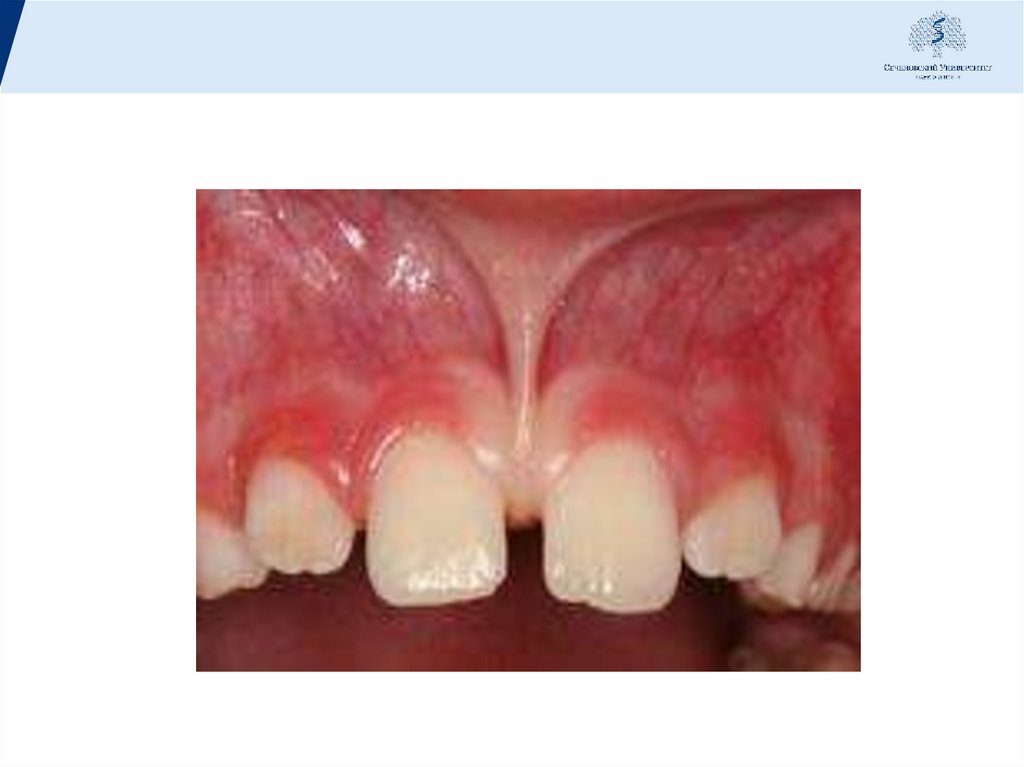

27. Клиника

• Начальная стадия:кровоточивость, отек десны, болевые

ощущения в области десен, зуд и жжение, неприятный

запах изо рта. Можно обнаружить неглубокие

зубодесневые карманы, преимущественно в области

межзубных пространств.Зубы неподвижны, не смещены и

нет явных признаков нарушений общего состояния

организма. на рентгенограмме определяются отсутствие

компактной пластинки на вершинах межзубных

перегородок, расширение периодонтальной щели в

пришеечной области, резкие очаги остеопороза и первые

признаки деструкции костной ткани.